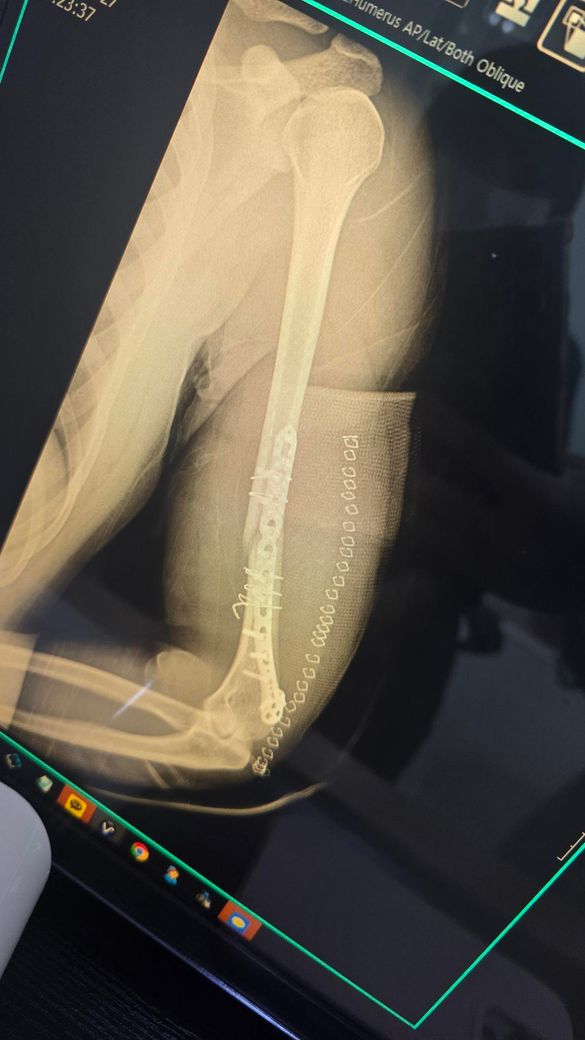

현재 골절 수술후 106일차에요.. 8도정도 틀어졌고 정복이 잘 안됐다고 하는데 아직은 기다려볼 단계일까요 진료는 여러군데 더 예약해놨어요.. 수술부위는 좌우 움직일 때 뼈소리 자주나요

엑스레이상 상완골 원위부의 분쇄골절로 인해 정복이 완벽하지 않고, 금속판 주위로 일부 각변형이 관찰되는 상태입니다.

수술 후 100일이 넘은 시점에서 골절선이 여전히 뚜렷하게 보이며 빈 공간을 채우는 뚜렷한 골진형성이 다소 더뎌 보여 부정유합이나 불유합의 가능성을 염두에 두어야 하는 시기인것은 맞습니다. 다만 부정유합은 뼈가 아예 붙지 않는것이 아니라 잘못된 모양으로 붙는것을 의미하며, 현재의 각도가 기능에 큰 지장을 주지 않는다면 무조건적인 재수술보다는 경과를 더 지켜볼수도 있습니다. 움직일때 나는 소리는 골절부위의 미세한 움직이미 때문일수 있으므로 절대적인 안정과 추가적인 고정이 필요할수 있습니다. 예약된 진료를 통해 골유합진행 여부를 면밀히 확인하시길 권합니다. 빠른쾌유를 빕니다!

• 제시된 영상은 상완골 간부 골절에 대해 금속판 고정술 시행 후 약 3개월 경과한 상태로 보이며, 골절 부위의 정렬은 유지되고 있으나 피질 연속성이 완전히 회복되었다고 보기는 어렵고 가교성 골진 형성도 충분히 성숙한 형태로 뚜렷하게 보이지는 않습니다. 초기 전위가 있었고 현재 약 8도 정도의 각형성이 남아 있는 점을 고려하면, 현재 단계에서 가장 우선적으로 의심되는 것은 부정유합이라기보다는 지연유합입니다.

상완골 간부 골절은 다른 장관골에 비해 유합이 늦는 경우가 흔하며, 수술 후 3개월 시점에서는 유합이 진행 중일 수 있는 시기입니다. 다만 이 시기에 골진 형성이 부족하거나 골절선이 여전히 명확하게 남아 있다면 향후 유합 지연 또는 불유합으로 진행할 가능성이 있어 주의가 필요합니다. 8도 정도의 각형성은 기능적으로 허용 범위에 속하는 경우가 많으나, 회전 변형이나 통증, 기능 제한이 동반되면 임상적 문제로 이어질 수 있습니다.

움직일 때 느껴지는 소리는 단순 연부조직 마찰일 수도 있으나, 골절 부위의 미세한 움직임이나 고정 안정성 부족을 시사하는 경우도 있어 경과 관찰에서 중요한 단서가 됩니다. 특히 통증이 지속되거나 점차 증가하는 양상이면 유합 지연 또는 고정 실패 가능성을 더 신중하게 봐야 합니다.

현재 시점에서는 즉시 재수술을 결정하기보다는 유합 진행 여부를 객관적으로 평가하는 것이 중요하며, 단순 방사선 외에 CT를 통해 골절면의 실제 연결 여부를 확인하는 것이 도움이 됩니다. 일반적으로 수술 후 3개월에서 6개월 사이에 유합이 진행되지 않거나 정체되는 경우, 또는 통증과 기능 저하가 지속되는 경우에 재수술을 고려하게 되므로, 현재는 다기관 진료를 통한 2차 의견과 함께 일정 기간 추적 관찰을 병행하는 접근이 타당한 단계로 판단됩니다.